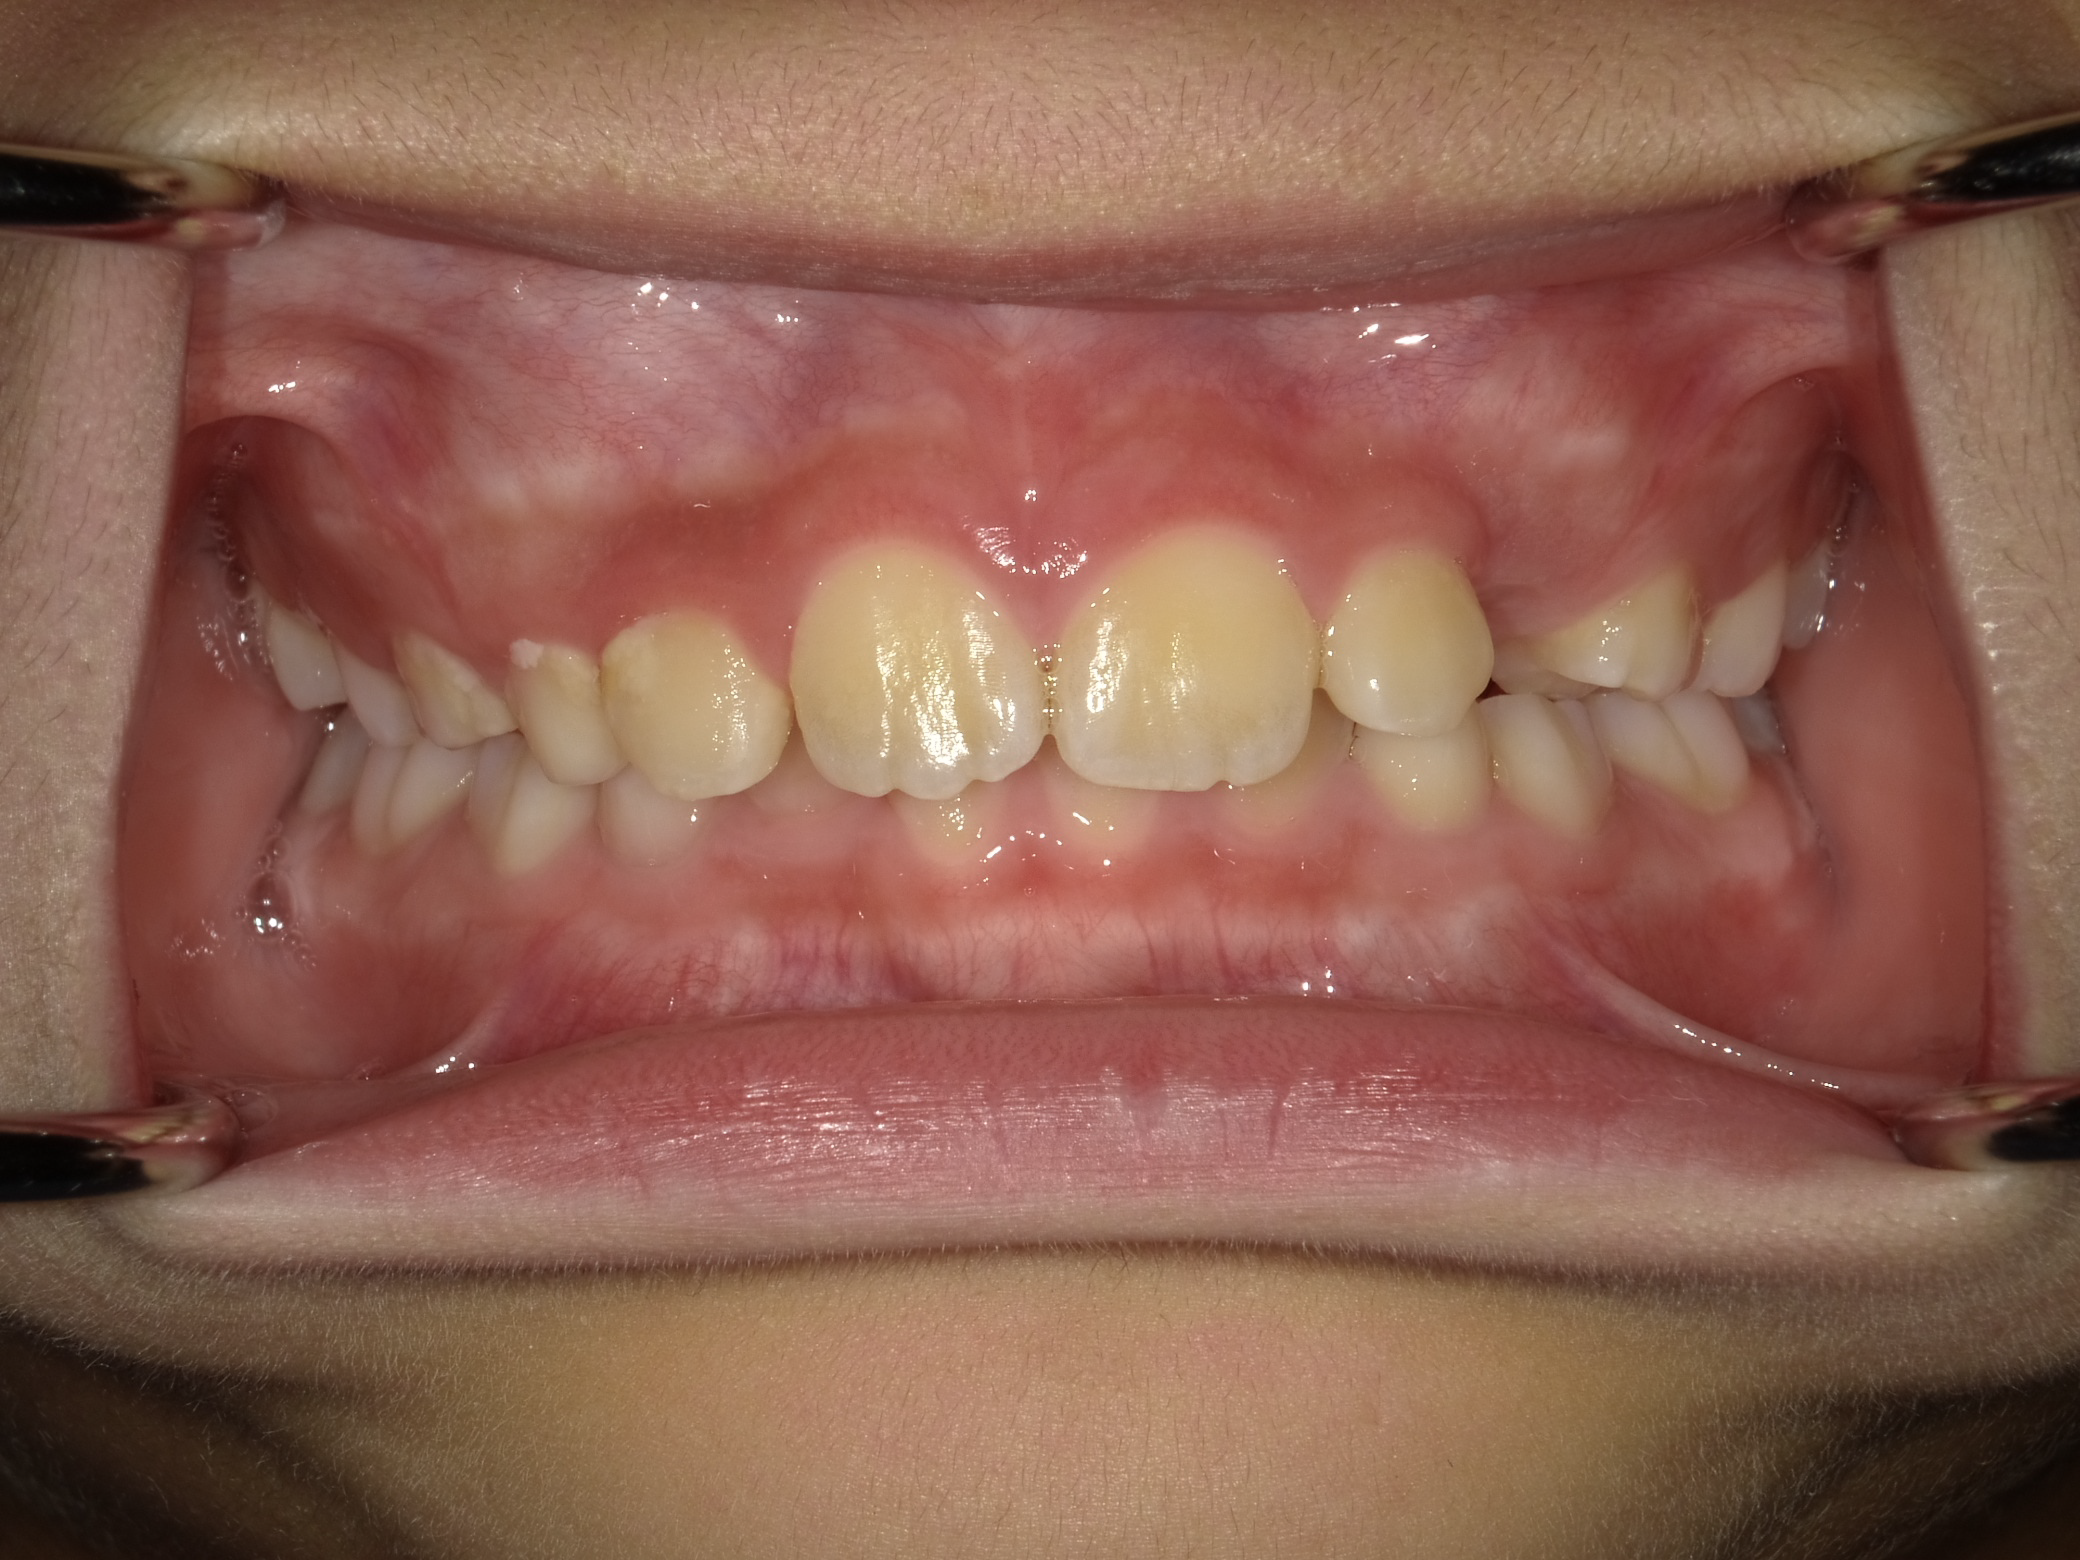

治療前の状態

下の前歯も左右とも内側に生えている歯が並ぶスペースがなく、このままでは凸凹の状態が残ります。

また、横顔を見ても上唇が突出し、上顎前突(いわゆる出っ歯)の状態です。上の歯が下の歯を全て覆い前から見ても下の歯が見えません。

このままでは、将来的に奥歯の負担が大きくなり、歯を失う原因になる可能性があります。叢生(凸凹)の改善と、上顎前突の改善を目的に1期矯正を開始しました。